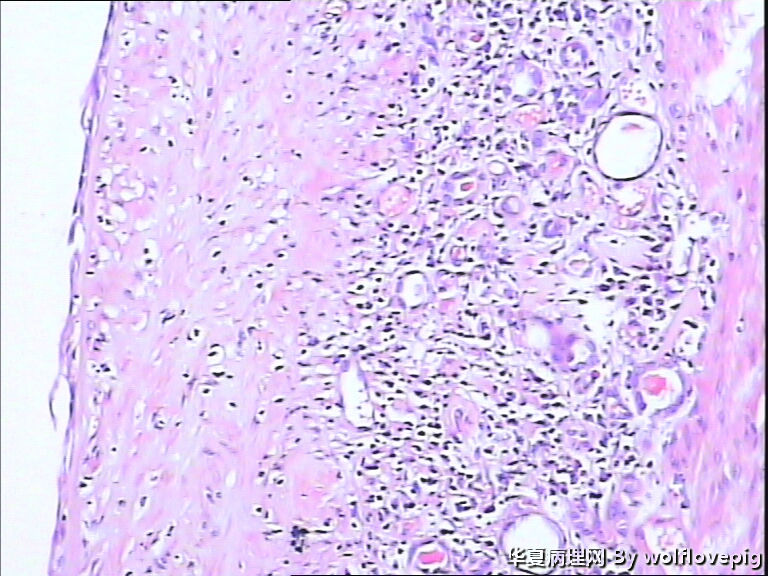

男,70y,左腰痛一年,反复血尿1月,坐肾区轻叩痛。